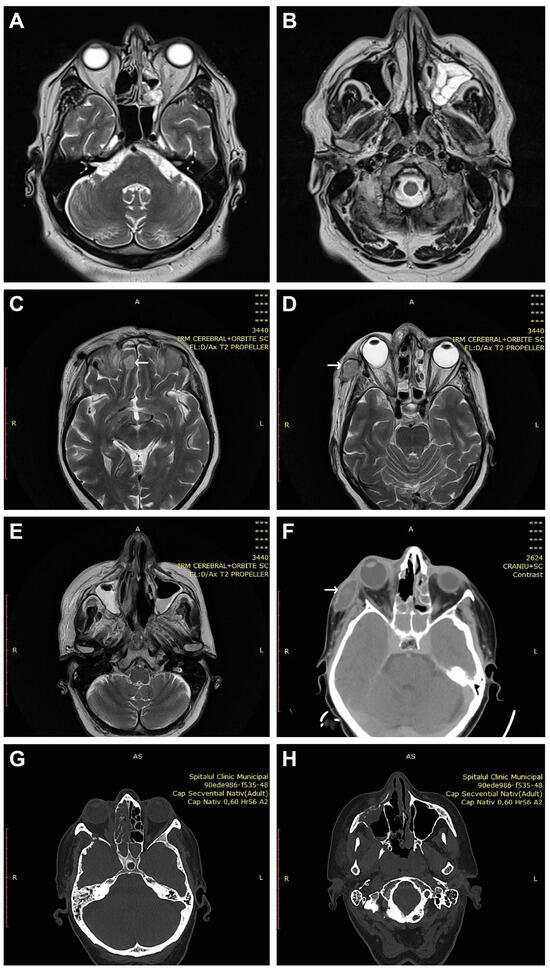

The immobility of the eye, exophthalmos, incomplete or complete blepharoptosis, and swelling of the zygomatic region were observed in the facies (Figure 1). Figure 2 shows CT and MRI preoperative radio-imaging aspects, and Figure 3 shows intraoperative aspects during FESS.

Figure 2.

Two CT and MRI radio-imaging aspects in CAM. (A,B) Left exophthalmos and left maxillo-ethmoidal rhinosinusitis. (C) Right paramedian frontal cerebral intraparenchymal abscess (arrow). (D–F) Altered sphericity of the right eyeball, pansinusitis with inhomogeneous content, and zygomatic abscess (arrows). (G,H) Right pansinusitis and bone erosions.

Affection of the nasal fossa (Figure 3A–D,G–J) and the homolateral maxillary sinus was observed in all patients included in the study (Figure 2B,E,H). The extension of lesions to all paranasal sinuses on the same side was observed in half of the patients (50%, n = 4/8). The extension of the lesional process at the level of the orbit was observed in 62.5% of patients (n = 5/8) (Figure 1A–D and Figure 2A,D,F), 25% of patients (n = 2/8) presented oral invasion (Figure 3E,F,K), 25% of patients (n = 2/8) presented invasion in the zygomatic region (Figure 1B,D and Figure 2D,F), and one patient (12.5%, n = 1/8) presented cerebral invasion (Figure 2C).